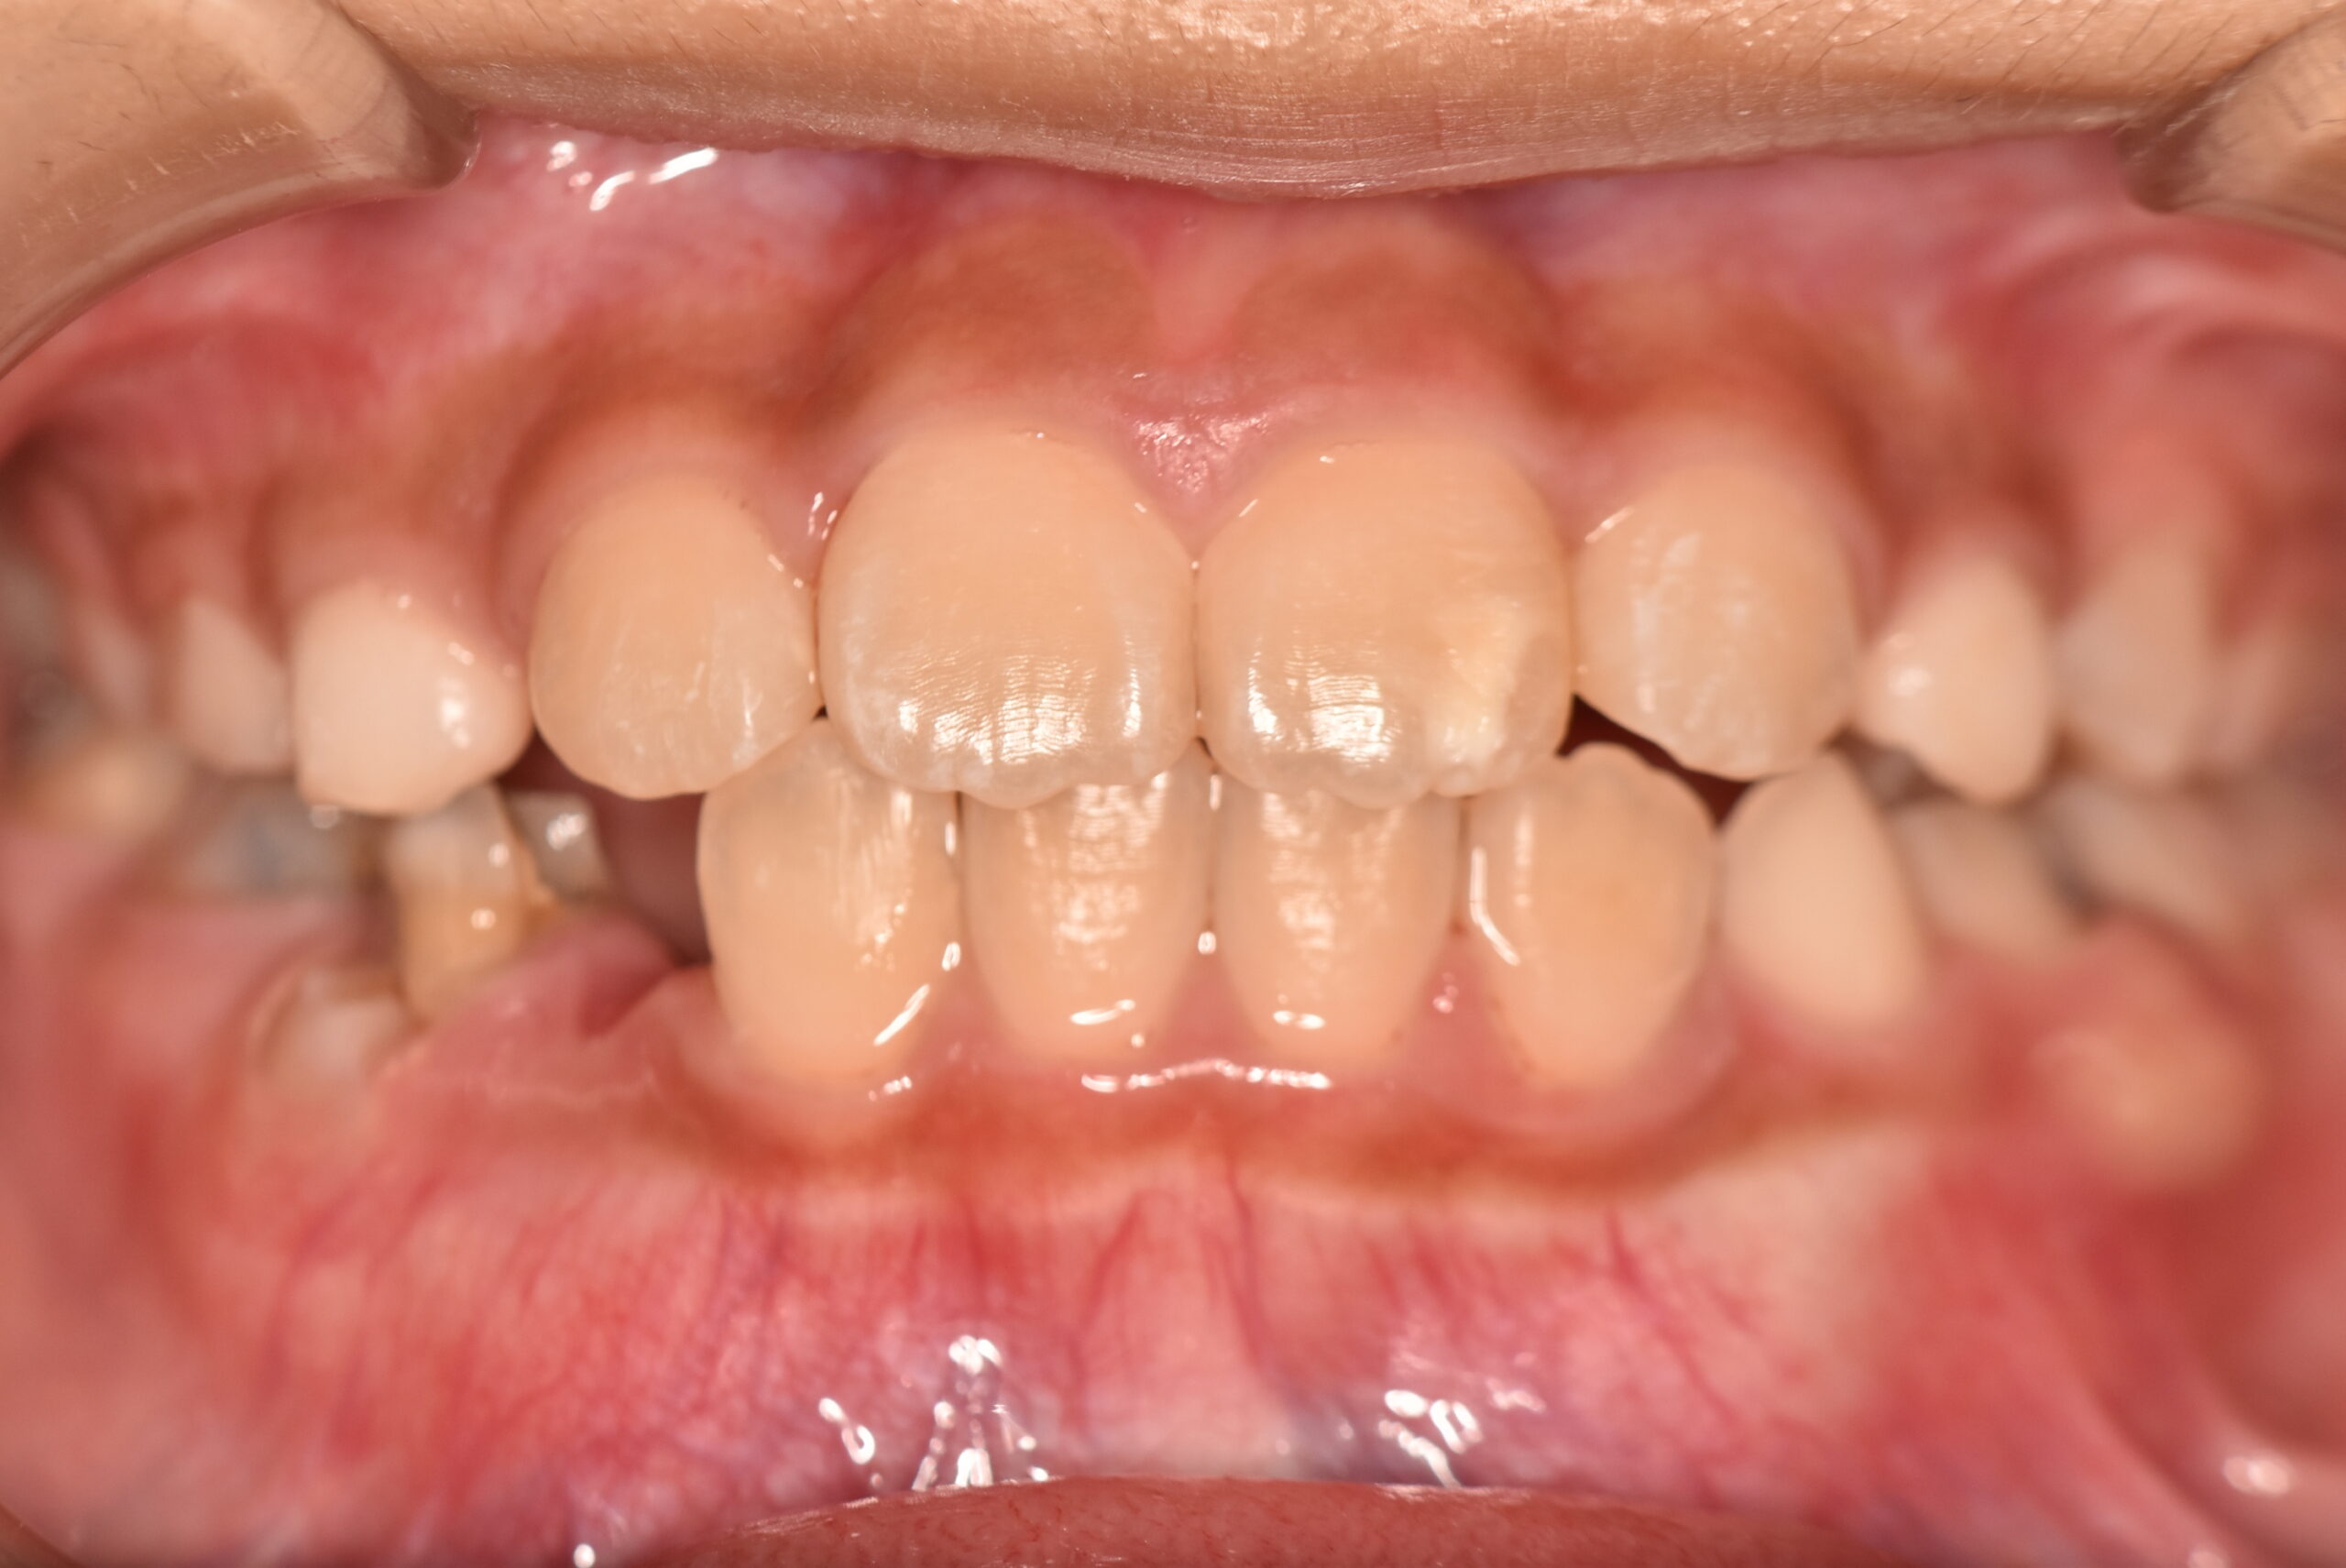

インビザラインファースト 【2724】

初診時

症例 症例 症例 症例

年齢

8歳 性 別 女性

治療期間 6ヶ月 費 用 矯正施術料:800,000円

調整料:4,000円/月

治療内容の詳細 初診時8歳の女児で、正中のズレを気にされ来院されました。

検査の結果、臼歯部交叉咬合を伴うアングルⅠ級不正咬合と診断しました。

治療としてはマウスピース矯正(インビザラインファースト)で配列を行い、上顎の側方拡大と萌出スペースを確保しました。

治療期間は、6ヶ月でした。

今後、側方歯生え変わりまで経過観察を行います。